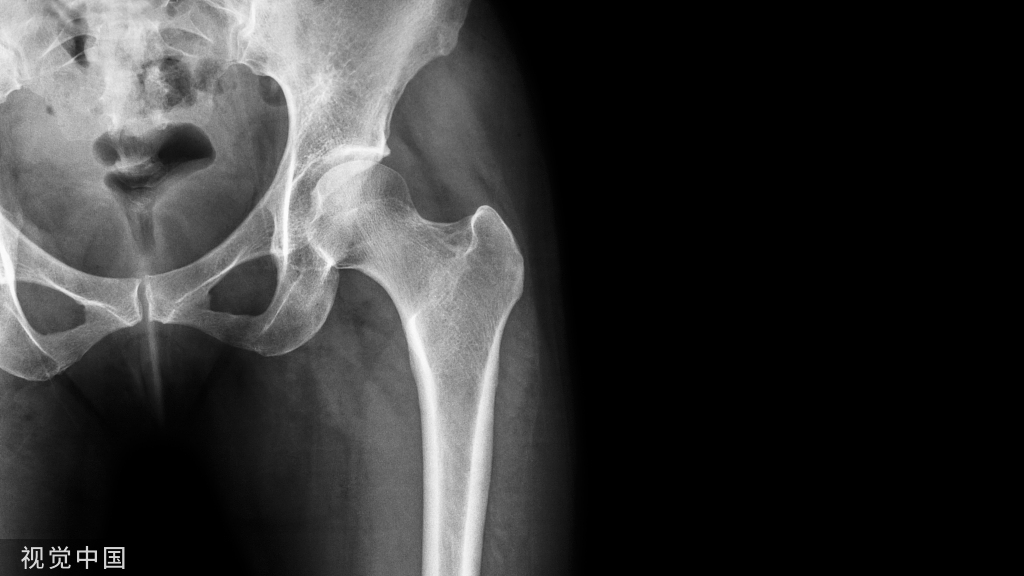

4、大粗隆骨折